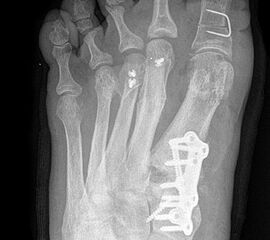

Die dorsoplantaren Röntgenaufnahmen zeigen eine Open-wedge Technik mit der normalerweise ein erhöhter intermetatarsaler Winkel gut zu korrigieren ist (Abbildung 3). Die Wirksamkeit einer Basisosteotomie ist umso größer, je proximaler diese durchgeführt wird. Je weiter distal die Osteotomie, umso geringer die Korrektur. Auf den postoperativen Bildern ist der distal unverändert große Abstand zwischen Metatarsale I und Metatarsale II erkennbar, bei gleichzeitiger Subluxation des Großzehengrundgelenks und dezentrierten Sesambeinen. Darüber hinaus finden sich initiale degenerative Veränderungen im Großzehengrundgelenk. Klinisch bestand eine hohe Weichteilspannung, bei verkürzter Extensor- und Flexor hallucis longus Sehne.  Daher wurde ein verkürzendes Verfahren zur Revision gewählt (Abbildung 4). Die Lapidusarthrodese stellt ein sehr zuverlässiges Verfahren zur Behandlung von Hallux valgus Rezidiven dar 9. Die Fusion des Tarsometatarsale-I-Gelenks kombiniert Stabilität mit einem hohen Korrekturpotenzial. Aufgrund der verfahrensimmanenten Verkürzung des ersten Strahls und der in diesem Fall bereits präoperativ vorhandenen Transfermetatarsalgie wurde die Entscheidung für eine verkürzte Weil-Osteotomie am zweiten bis fünften Strahl gefällt. Die Kombination beider Verfahren führte zu einem homogenen Metatarsale-Index und zu einer gleichmäßigen plantaren Druckverteilung 10. Die Hallux valgus interphalangeus Fehlstellung wurde mit einer Akin-Osteotomie korrigiert.